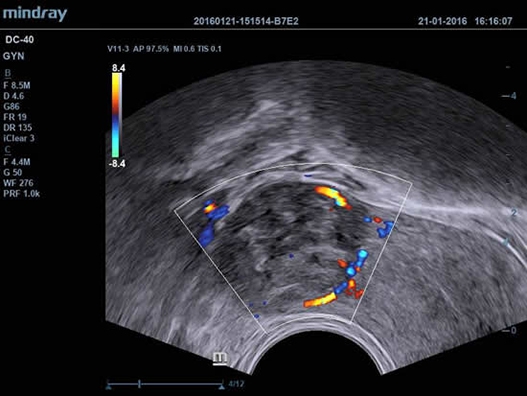

• Shared Service Package - предустановленные параметры, аннотации, маркеры, программы измерений для абдоминальных исследований, акушерства, гинекологии, кардиологии, ангиологии, исследований малых органов, урологии, педиатрии, неотложной медицины;

• Внутриполостной датчик Mindray V11-3